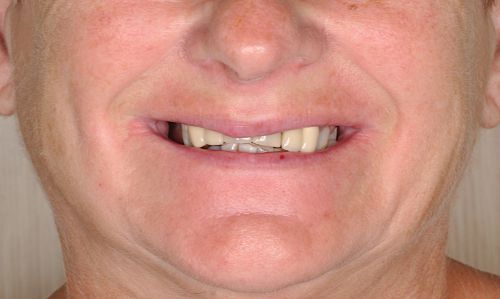

Pani Teresa

Wykonana praca protetyczna:

- korony pełnoceramiczne na zębach własnych górnych

- korony na implantach w miejscach braków zębów górnych

- mosty na implanatch w łuku dolnym

- odbudowa flow-injection zębów dolnych przednich

Praca wykonana przez: dr n. med. Michała Kubiszyna, lek. dent. Annę Andrzejewicz-Melaniuk

Leczenie zachowawcze i endodontyczne: Lek. dent. Anna Andrzejewicz-Melaniuk